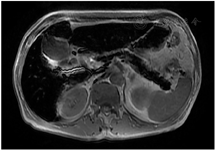

影像学检查:头颅MRI(图2)提示双侧额颞顶枕叶皮质下及基底节区低信号,考虑代谢性脑病可能。腹部MRI(图3)提示肝实质和胰腺T1WI及T2WI+FS信号弥漫性减低,均呈极低信号。腹部超声提示肝脏轻度纤维化、肝左叶体积增大,脾轻度肿大,胰腺萎缩伴纤维化、双肾体积缩小、前列腺体积缩小。睾丸超声提示双侧睾丸萎缩。骨密度提示左侧股骨颈骨密度(bone mineral density, BMD)测量值符合骨质疏松(腰椎L1-4 BMD为0.879 g/cm2,T值-1.7,Z值-0.5;左股骨颈BMD为0.638 g/cm2,T值-2.6,Z值-1.2;左股骨上端为0.731 g/cm2,T值为-2.0,Z值为-1.4)。心电图示窦性心动过缓、异常"Q"波。

临床上血色病通常因实验室检查提示血清铁蛋白或转铁蛋白饱和度升高而发现,但上述两项指标特异性较低,往往需要进一步检查来明确诊断[2]。影像学是诊断血色病的重要辅助检查,当肝脏、脾脏和胰腺等脏器出现铁超载时,因铁的超顺磁性效应,MRI-T2加权序列可表现出明显低信号[3]。若肝实质内铁含量>7 mg/g肝重量时,MRI-T2序列图像可出现"黑肝症",这对量化和可视化血色病患者肝脏铁含量具有重要意义[4]。本例患者MRI-T2序列可见肝实质信号弥漫性减低,表现为明显"黑肝症",除此之外胰腺和双侧额颞顶枕叶皮质下及基底节区也出现信号缺失,提示本例患者肝脏、胰腺,甚至是脑部均可能存在铁超载。